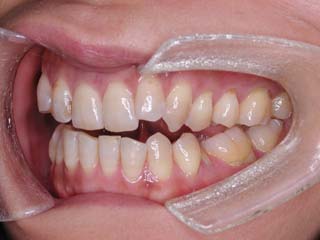

主訴:前歯の噛み合わせ

診断名:叢生を伴う開咬

年齢:28歳

使用した主な装置名:TPB、上顎リンガルブラケット矯正装置、下顎マルチブラケット装置、オーソアンカー SMAPシステム

抜歯/非抜歯および抜歯部位:非抜歯

治療期間:動的処置2年1か月、経過観察3年

本症例について検査診断の結果、開咬、叢生、下顎前突傾向を認めました。患者希望を考慮し、治療メカニクスとして、非抜歯配列、上顎のみリンガルブラケット矯正装置、下顎唇側マルチブラケット矯正装置、および、目的外使用のオーソアンカー SMAPシステムを用いることにいたしました。